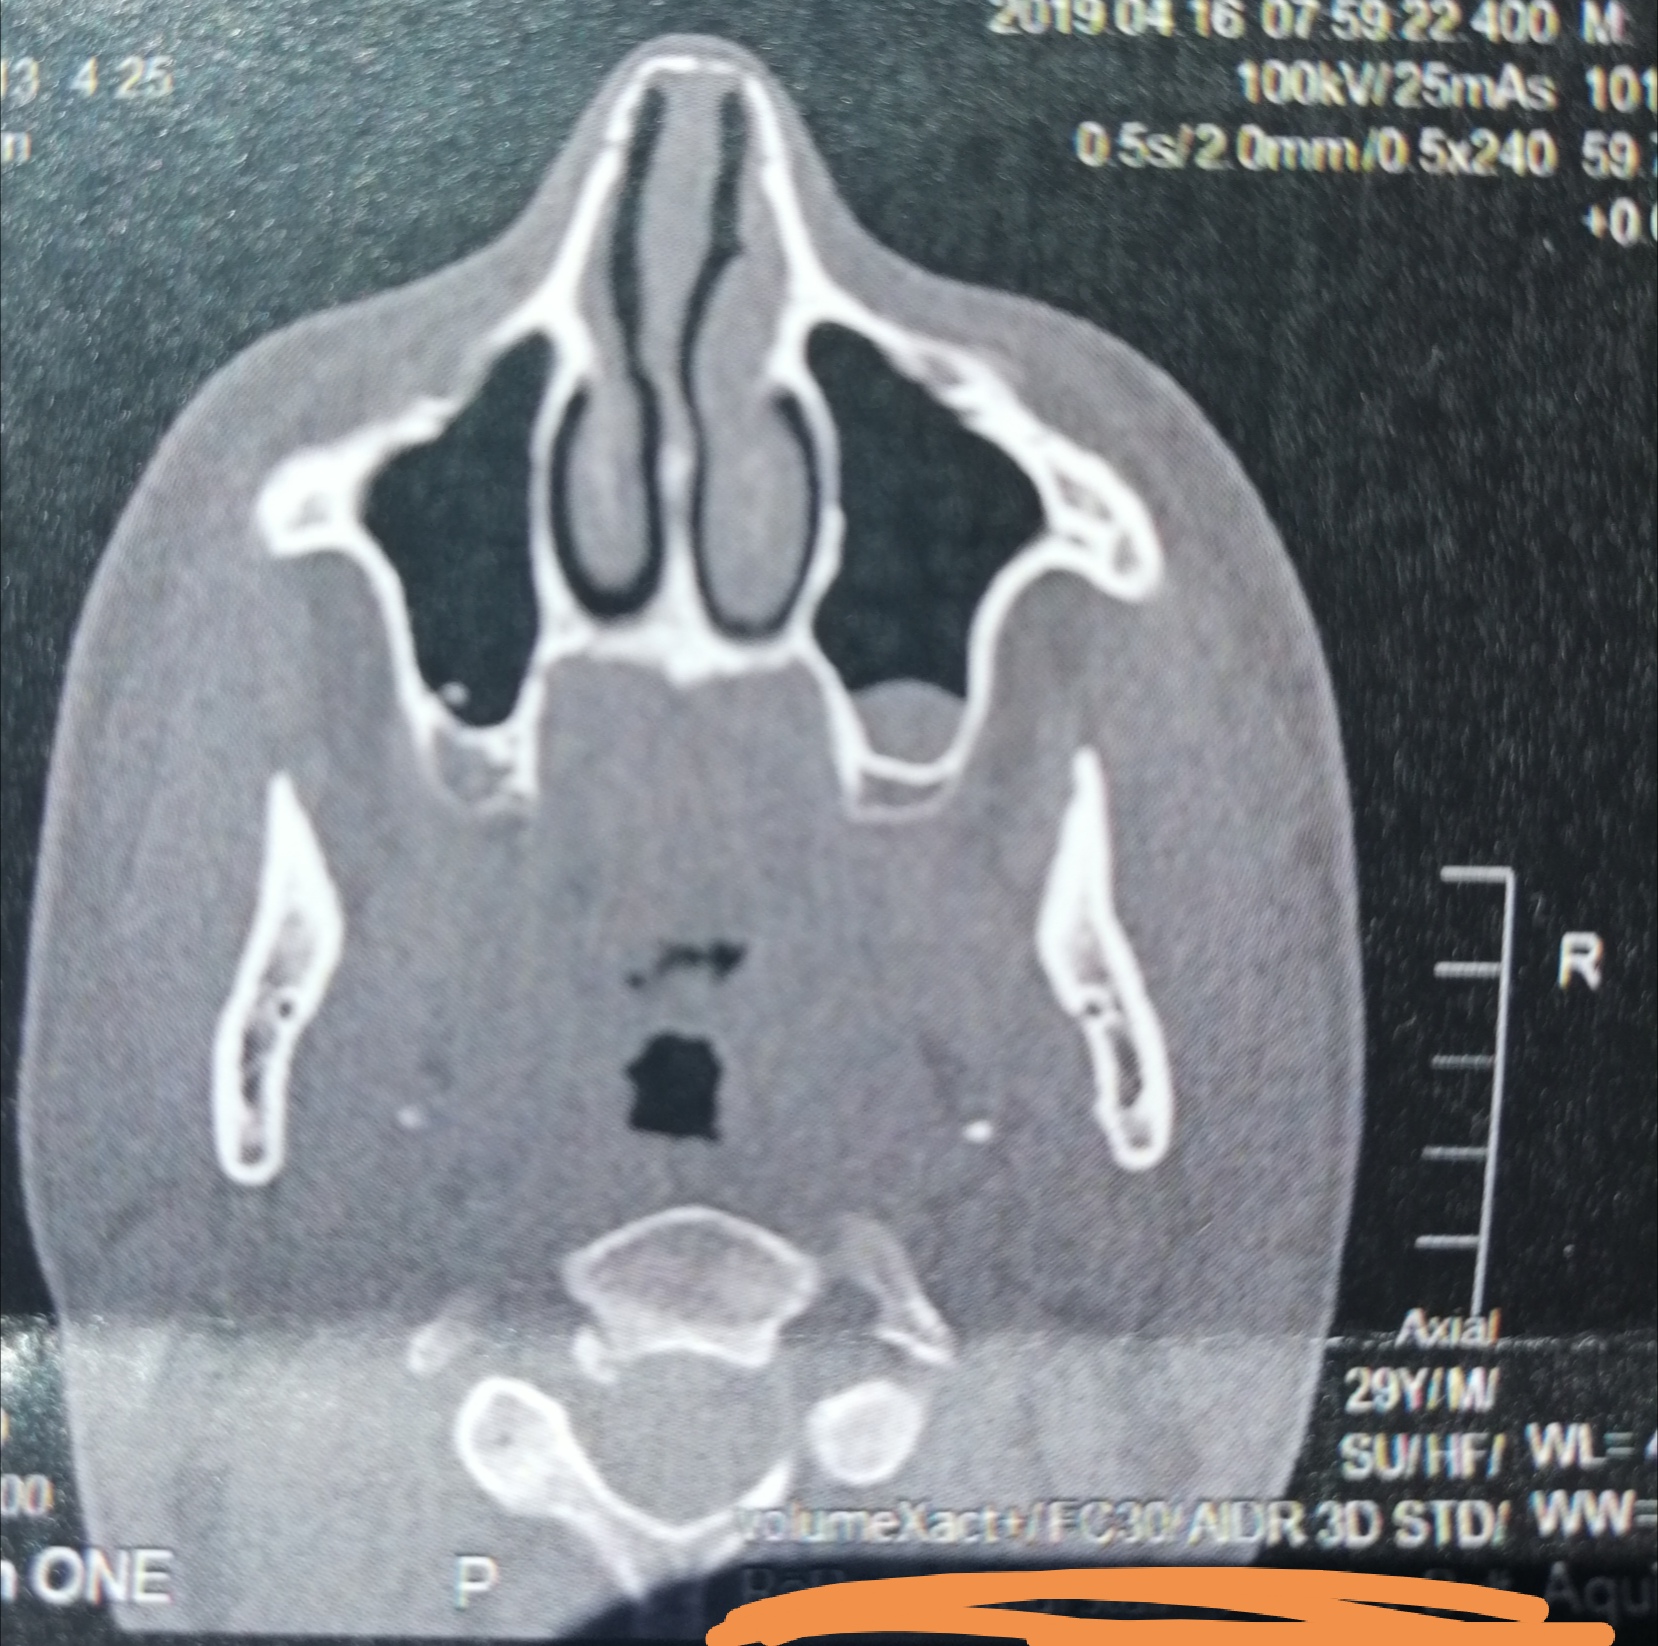

CT der Nasennebenhöhlen /Nase, alles ok? (kernspintomographie)

Source: www.gesundheitsfrage.net